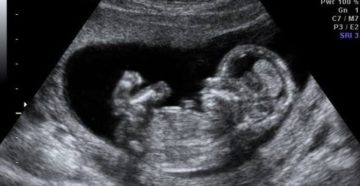

38 неделя беременности Тридцать восьмая неделя вполне может быть заключительным сроком беременности. Рожденный на 38-й…

38 неделя беременности — признаки, симптомы, описание 38 неделя беременности может стать как временем появления…